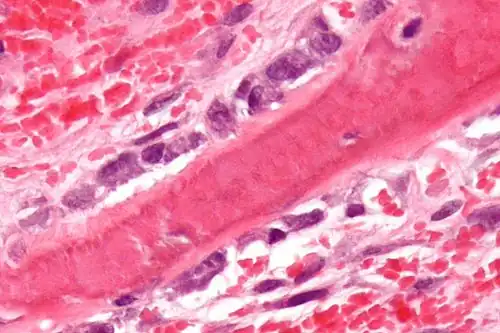

Osteoblasts (purple) rimming a bony spicule (pink - on diagonal of image). In this routinely fixed and decalcified (bone mineral removed) tissue, the osteoblasts have retracted and are separated from each other and from their underlying matrix. In living bone, the cells are linked by tight junctions and gap junctions, and integrated with underlying osteocytes and matrix H&E stain. | |

Morphology and histological staining

Hematoxylin and eosin staining (H&E) shows that the cytoplasm of active osteoblasts is slightly basophilic due to the substantial presence of rough endoplasmic reticulum. The active osteoblast produces substantial collagen type I. About 10% of the bone matrix is collagen with the balance mineral.[29] The osteoblast's nucleus is spherical and large. An active osteoblast is characterized morphologically by a prominent Golgi apparatus that appears histologically as a clear zone adjacent to the nucleus. The products of the cell are mostly for transport into the osteoid, the non-mineralized matrix. Active osteoblasts can be labeled by antibodies to Type-I collagen, or using naphthol phosphate and the diazonium dye fast blue to demonstrate alkaline phosphatase enzyme activity directly.

Osteoblasts lining bone (H&E stain)

Osteoblasts lining bone (H&E stain)